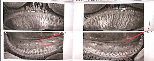

不出所料,一查发现杜先生下眼睑患有相对比较重的睑板腺功能障碍,同时在他的双眼睫毛内发现了大量螨虫,有的单个毛囊里甚至高达3、4条!

(图为杜先生下眼睑显示睑板腺部分丢失)